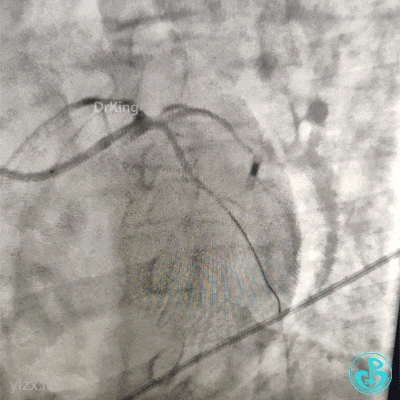

急诊造影

左冠脉造影发现左主干闭塞。

2.0×15mm球囊预扩张后。

植入4.0×13mm支架1枚。